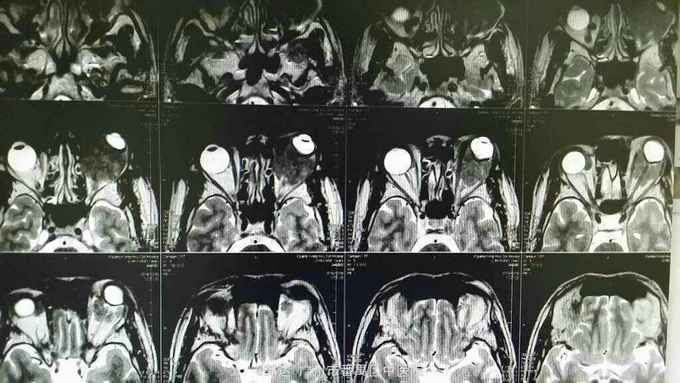

患者男性,41岁。左眼反复眼睑肿胀2年,加重伴眼球突出1月余。患者曾余当地医院行CT检查提示左眶病变,考虑血肿与占位性病变。诊断为左眶蜂窝织炎并予抗感染治疗,无明显好转。

检查:患者视力不配合,左眼眼球突出伴向外偏斜,左眼眶压T+1,左眼下睑红肿,下睑可触及肿块,大小约2*3cm,质地中,边界不清伴压痛,不可活动,余查体未见明显异常。眼部超声:左眼玻璃体混浊、视网膜脱离、脉络膜脱离声像。左眼眶实质性占位性病变声像。眼眶MRI提示左眼球后、右侧眼眶内上方多发占位性病变,考虑1、炎性假瘤2、淋巴瘤

诊断:双眼眶肿物、左眼陈旧性视网膜脱离 治疗:全麻下行眼眶肿物切除+周围神经嵌压松解+眶隔修补术

随访:术后病理为左眼眶非霍奇金B细胞淋巴瘤。 讨论:患者以双眼眶肿物为特征,多见为淋巴瘤、炎性假瘤,两者在临床和影像上均类似,最后鉴别需要病理证实。术后应辅以全身化疗。